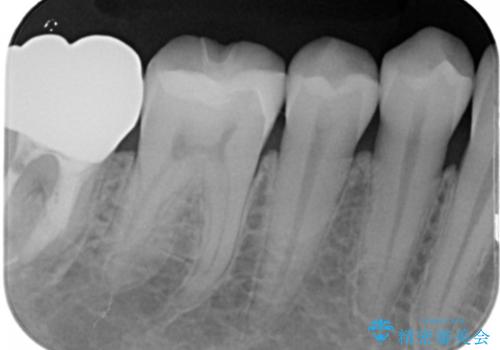

- 過去に他院で治療した部位が材料劣化を起こしていたため、セラミック治療を希望された患者様です。

切削量を考慮し、セラミックインレーを選択しました。

虫歯が深かったので、CRを詰めた上で形態を整えています。